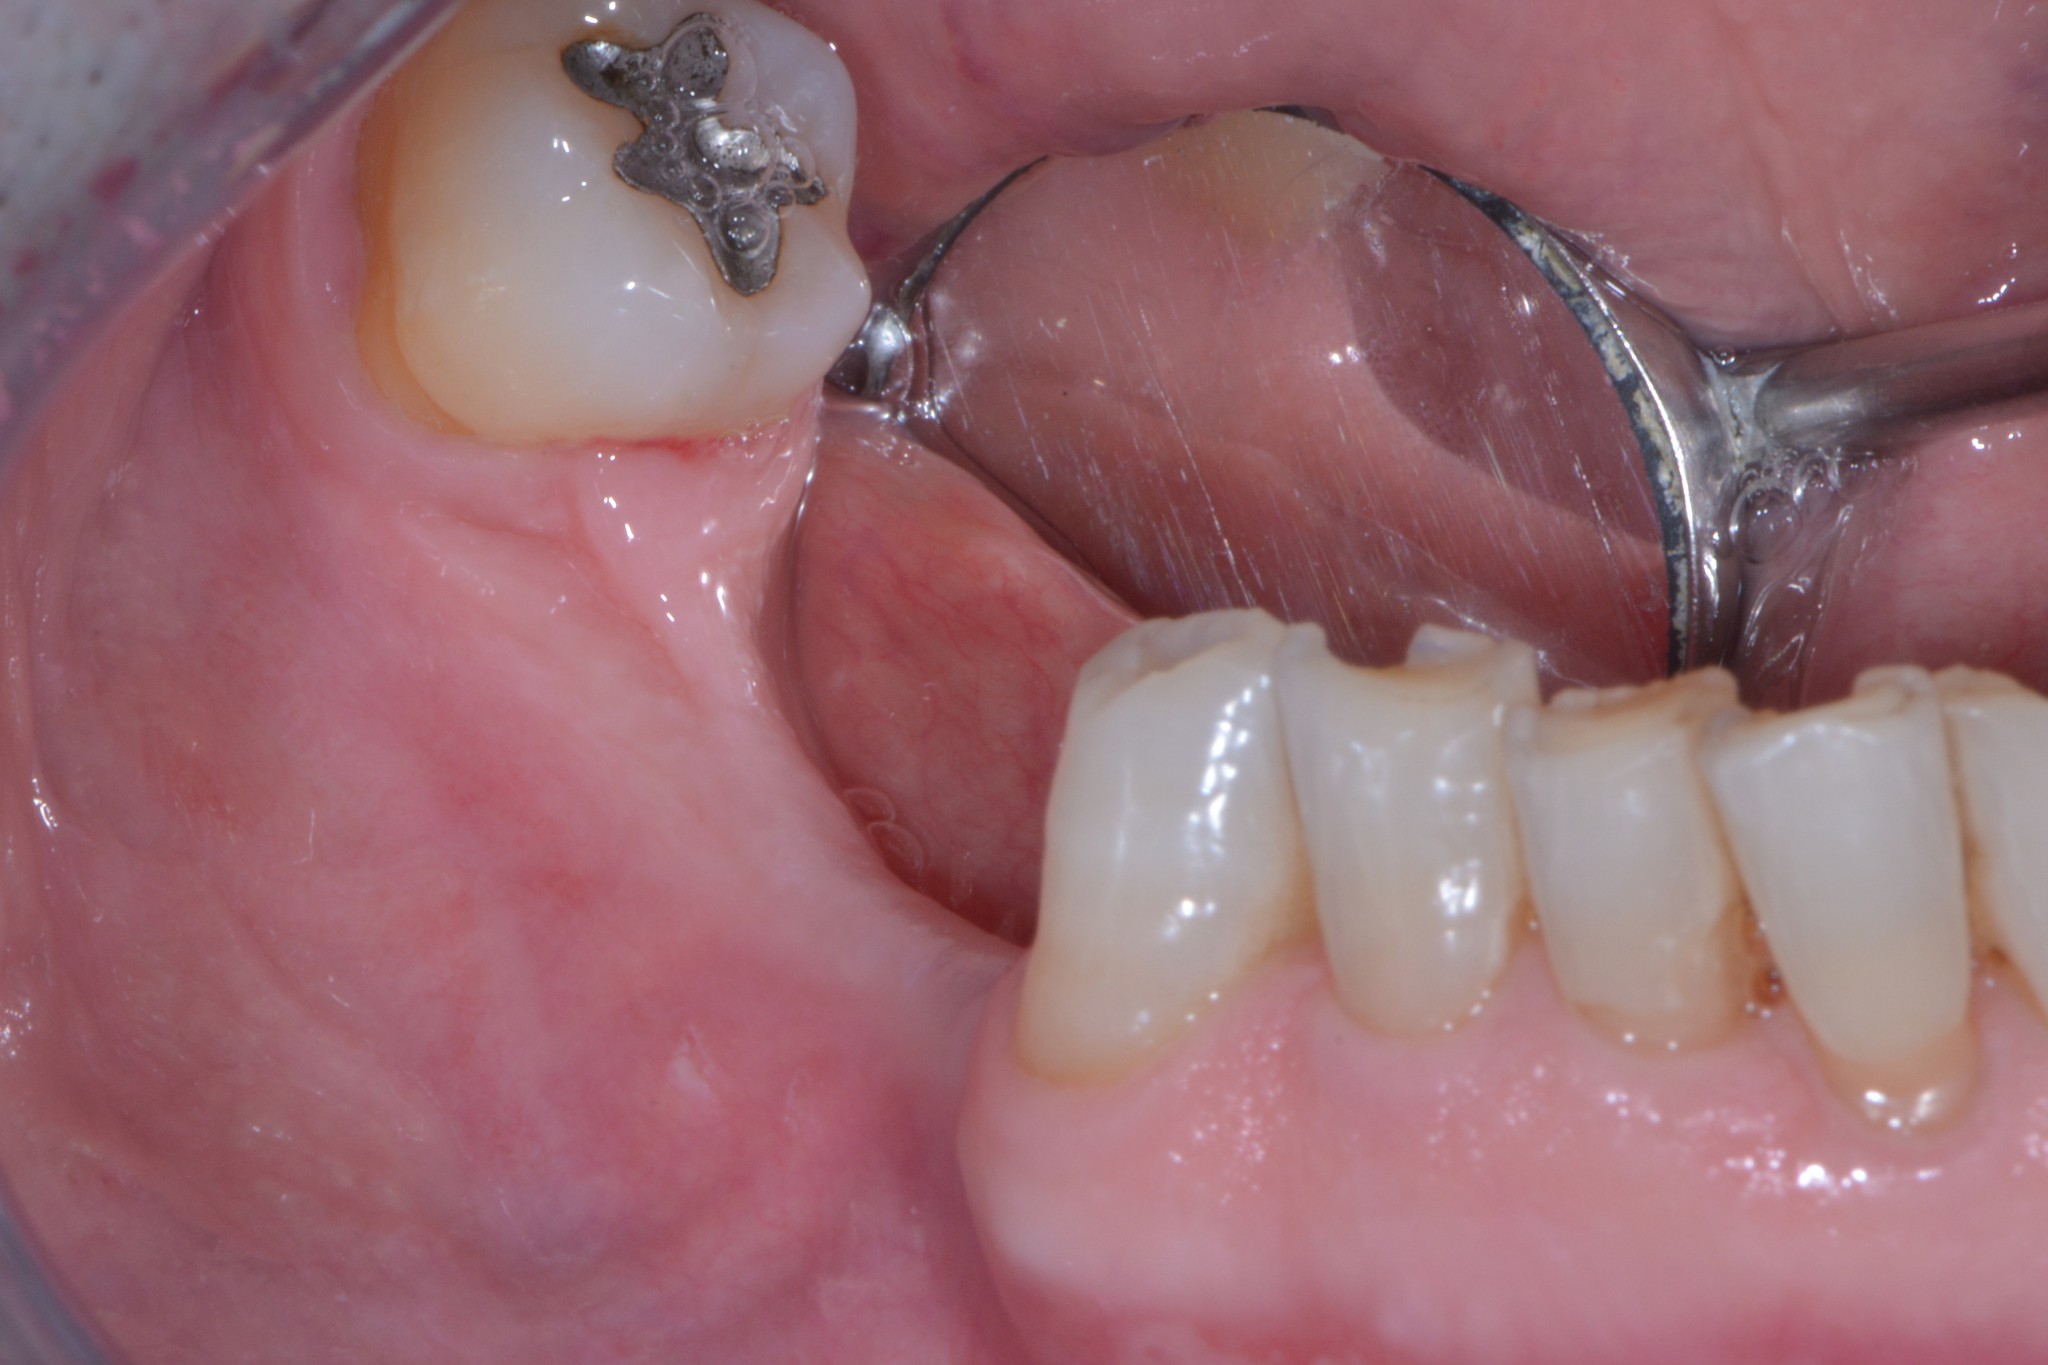

Il signor Franco, nostro paziente da quasi dieci anni, qualche mese fa ha finalmente deciso di mettere gli impianti che gli avevamo proposto nel lontano 2007. Già dalla foto dovresti notare una marcata atrofia verticale e orizzontale. Come mio solito faccio fare una radiografia tridimensionale per progettare l’intervento in sicurezza e spiegare al paziente esattamente cosa andrò a fare durante la seduta chirurgica…

Cosa vedi? Ok, una bella atrofia orizzontale, associata ad una modesta atrofia verticale. Come possiamo trattare una atrofia verticale associata ad una orizzontale? (rimanendo all’interno dell’evidence based medicine per carità!)

Te lo dico io: GBR (con vari tipi di barriere) o innesti a blocco. Io utilizzo entrambe le tecniche ma in questo caso, per una serie di motivi che forse un giorno discuteremo, ho optato per l’innesto a blocco.